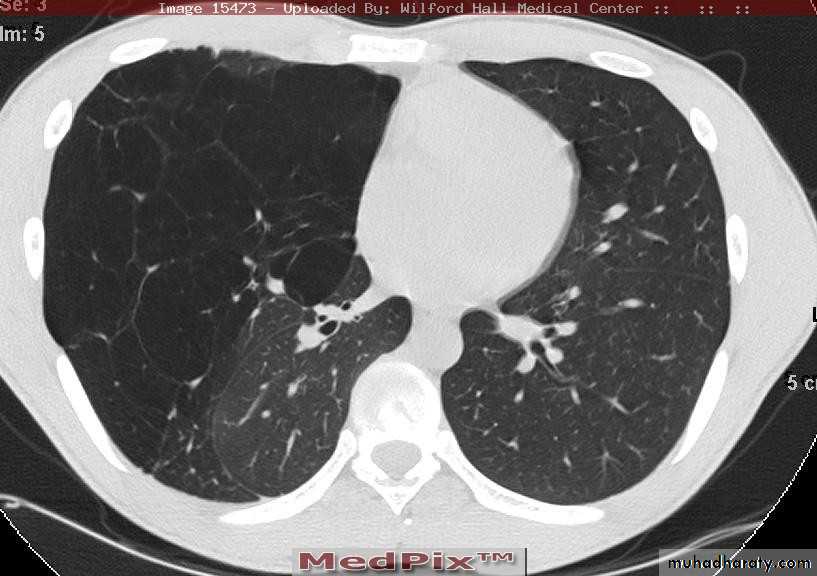

What is the difference??CT scan

BronchoscopyPneumothorax

Emphysema